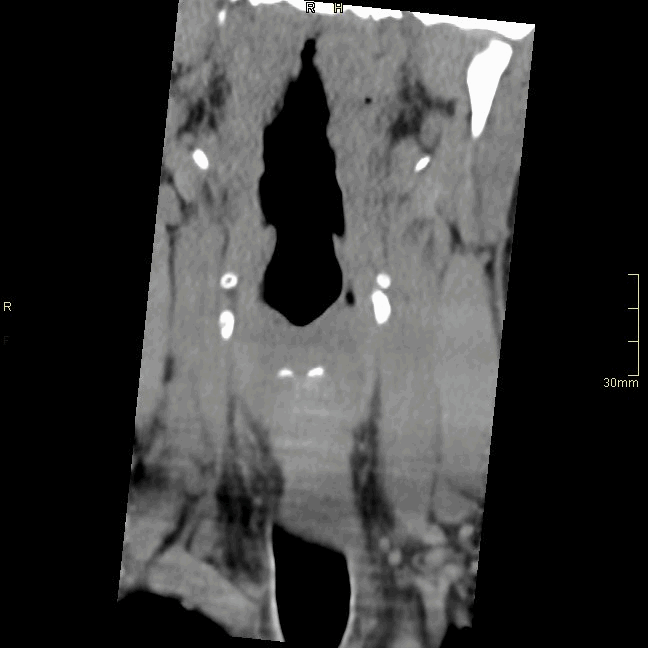

CT Cervical Spine Non Contrast- Bone window (axial)

CT Cervical Spine Non Contrast- Bone window (coronal)

CT Cervical Spine Non Contrast- Bone window (Sagittal)

CT Cervical Spine Non Contrast- Soft Tissue window (axial)

CT Cervical Spine Non Contrast- Soft Tissue window (coronal)

CT Cervical Spine Non Contrast- Soft Tissue window (sagittal)